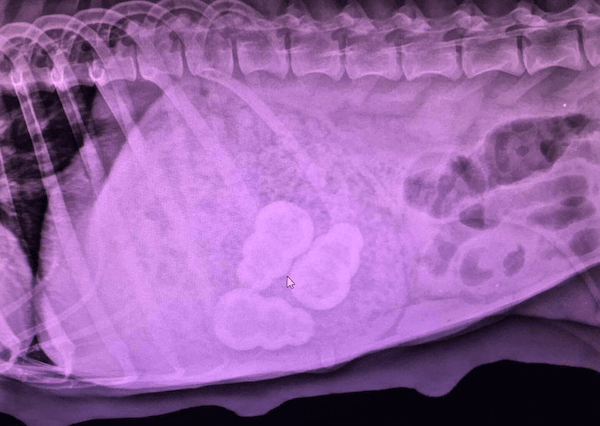

An important warning about choosing the correct size toys for your dogs, including when you have multiple dogs of different sizes. This photo is an X-ray of a dog’s abdomen.

Photo credit: Dr. Mandy Roberts, Hoschton Animal Hospital

The three snowman-shaped objects you see in the middle of the image are Kongs within the dog’s stomach! They wound up there, not because the dog’s owner intentionally gave their dog the wrong-sized Kongs, but rather because their child didn't supervise closely enough while this dog’s puppies were playing with their food-stuffed Kongs!

Mom perhaps decided that her pups were having too much fun and wanted in on the action. Or, maybe it was as it so often is, the kids just left their mess lying around for mom to clean up … and clean up this mom did!

She had to be taken to surgery to have these three Kong toys removed from her stomach. She came out unscathed, but the cost of surgery was an unfortunate consequence for the family.